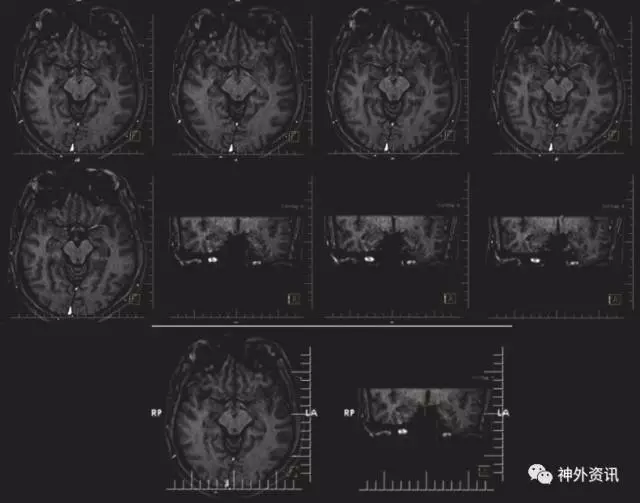

住院期间,患者发生3次不同类型的癫痫发作。第一次癫痫发作为睡觉醒来时双手强直性痉挛13秒;第二次发作为发作期终止前运动过多,头右偏22秒和轻微自动症;第三次发作持续1分9秒,头部右偏,右手伸展,左手外展,继而全身抽动以及发作期出现言语自动症。头颅MRI发现下丘脑、乳头体处错构瘤(图2),患者拒绝手术。

图2. 头颅MRI提示下丘脑、乳头体处错构瘤。